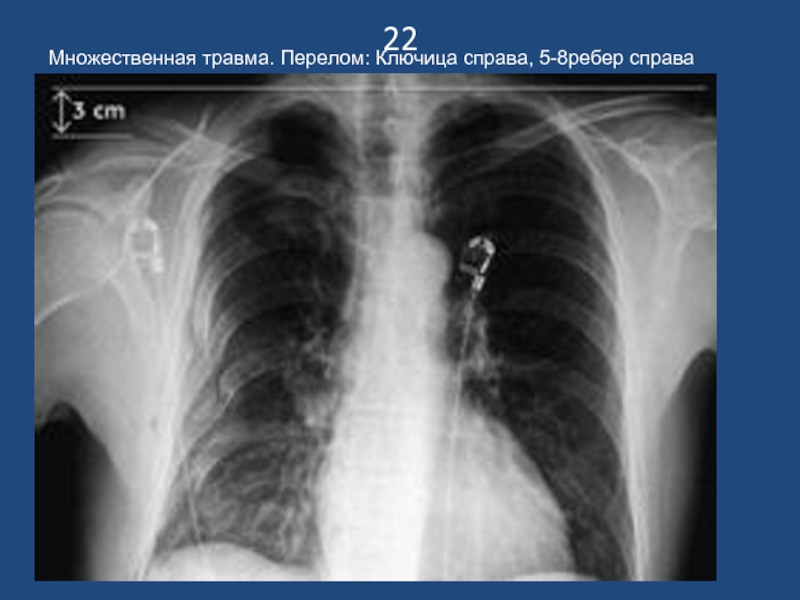

Слайд 2322

Множественная травма. Перелом: Ключица справа, 5-8ребер справа